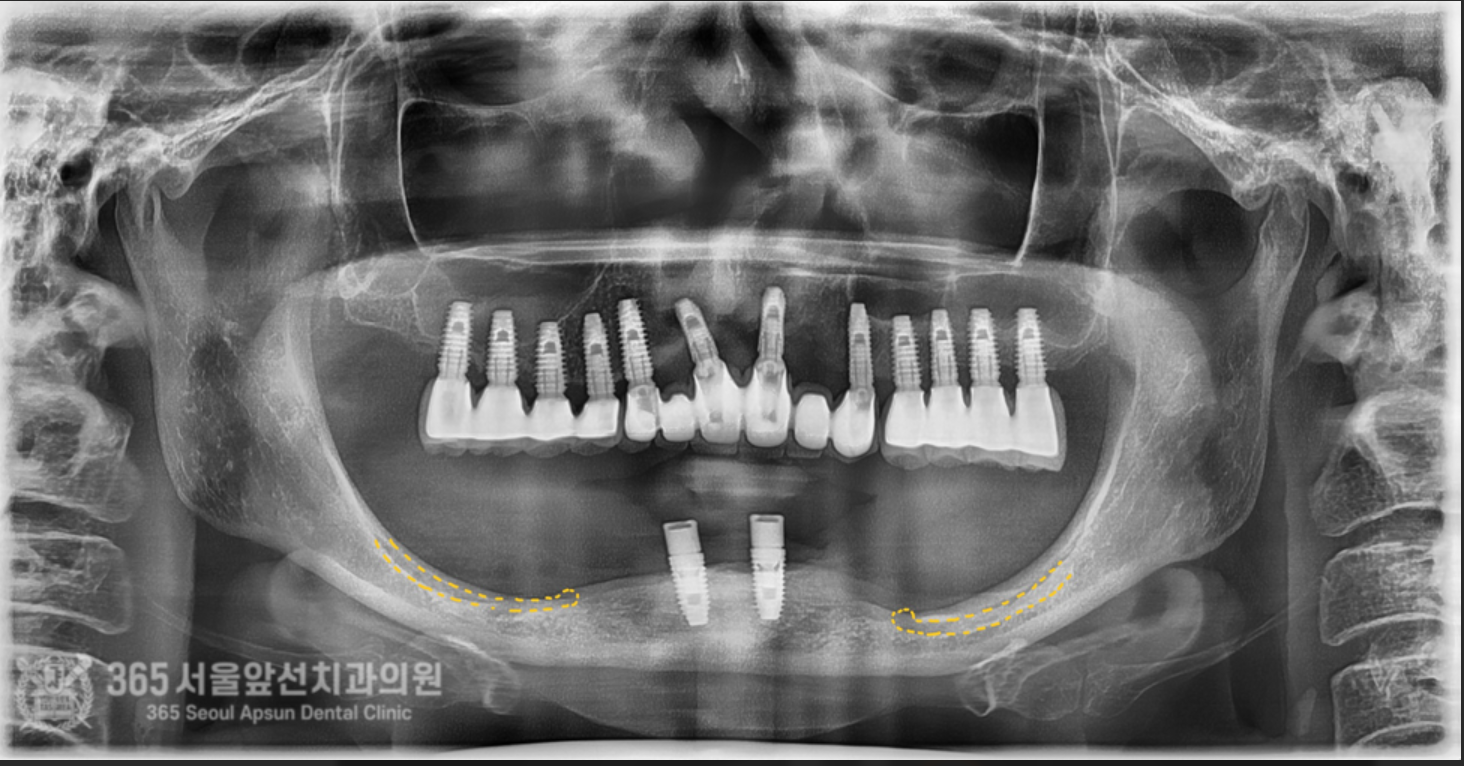

아래쪽에 임플란트 틀니를 썼었는데, 전체 임플란트 치료를 받고 싶어서 치과에 갔더니 뼈가 없어서 임플란트가 불가능하다고 판정받았어요. 촬영일시 : 2024.07.07. 처음 내원 당시 엑스레이 사진입니다. 촬영일시 : 2024.07.07. 사진에 노란색 표시를 한 곳이 신경관입니다. 보다시피 어금니 부위에는 뼈가 하나도 없습니다. 이 정도 뼈 상태라면 1000명의 환자분이 오신다면 그 중 단연코 1등으로 뼈가 안좋으신 상태 정도 됩니다. 기존의 임플란트는 제거를 해야하고, 이후 신경관을 피해서 5개의 임플란트를 식립하기로 했습니다. 촬영일시 : 2024.07.07. 수술 전 CT 사진으로 신경 구조물에 대한 정확한 사전 파악 후 수술에 들어갑니다. 왼쪽 아래턱 부위의 신경이 손상되지 않게 조심스럽게 수술을 진행했습니다. 오른쪽 아래턱 부위도 동일하게 신경이 손상되지 않게 조심스럽게 수술을 진행합니다. 기존 임플란트는 상태가 좋지 않아서 제거했습니다. 촬영일시 : 2024.07.07. 촬영일시 : 2024.11.16. 임플란트 수술 후 엑스레이입니다. 원하는 위치에 정확히 임플란트가 식립되었습니다. 임플란트가 뼈와 단단하게 굳으면 본을 떠줍니다. 정교한 보철물을 위해선 정확한 본뜨기 작업은 필수겠죠? 촬영일시 : 2024.11.16. 완성된 보철물입니다. 촬영일시 : 2024.11.16. 대략 4개월에 걸쳐 치료를 완료해드렸습니다. 환자분께서는 아주 만족하셨습니다. 정확한 임플란트 수술을 통해 신경 손상없이 성공적으로 마무리할 수 있었습니다 ㅎㅎ 촬영일시 : 2024.07.07. / 2024.11.16. 보철물 장착 전후의 입술 모습의 변화를 볼 수 있습니다. 입술이 볼록하게 지지받아서 자연스러운 안모로 변화했습니다. 촬영일시 : 2024.07.07. / 2024.11.16. 전후 구강내 사진입니다. 잇몸뼈가 많이 없으셔서 잇몸 부위를 핑크색이 나는 재질로 채워드렸습니다. 임플란트 불가능 판정을 받으셨던 환자분이신데 치료가 잘 마무리 되어 뿌듯했습니다 ㅎㅎ 신경관이 근접한 고난이도 임플란트 치료지만 충분한 경험과 지식이 있다면 치료가 가능하니 걱정 안하셔도 되겠습니다. 지금까지 365일 열린 가까운 서울대학교 치과병원을 지향하는 365서울앞선치과였습니다. 감사합니다. [ 치료기간 : 2024년 7월7일 ~ 2024년 11월 16일 ] ※ 365서울앞선치과의원의 모든 포스팅은 각 진료과 의료진이 직접 작성합니다. 365서울앞선치과의원 블로그의 임상 케이스 게시물은 환자분께 의학적으로 정확하고 상세한 정보를 드리기 위해 각 진료과 의료진이 직접 작성하며, 모든 증례 사진은 본원 의료진이 직접 시술한 증례를 촬영한 것으로, 의료법 제23조, 제56조에 의거하며 환자분의 동의를 얻어 포스팅에 사용하였습니다. 또한 해당 케이스는 본 환자분의 치료 결과이며, 환자 상태에 따라 치료의 결과는 달라질 수 있습니다. |